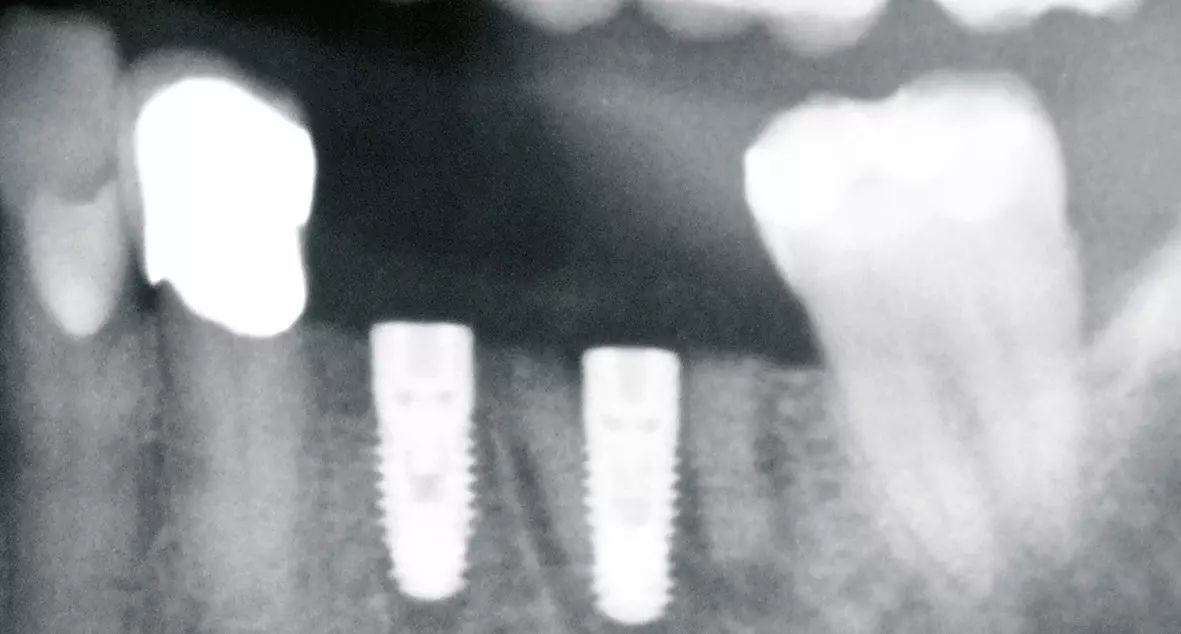

Nach 6 Monaten Einheilzeit wurde für eine exakte Planung präoperativ ein OPG und ein DVT angefertigt und die genauen Implantatpositionen mittels Software ermittelt (Abb. 4 a-c). Klinisch und radiologisch stellte sich ein ausreichendes Knochenangebot für eine Implantation dar (Abb. 3 und 4).

Vor dem abschließenden spannungsfreien und speicheldichten Wundverschluss (Abb. 10) erfolgte die Abdeckung der Implantate und des Knochenaufbaus mit einer Kollagen- (Geistlich Bio-Gide®, Geistlich Biomaterials) und PRF-Membran (Abb. 9). Das postoperative Röntgenbild (Abb. 11) zeigt die entsprechend der Planung gesetzten Implantate mit aufgeschraubten Heilungskappen. Zehn Tage postoperativ konnten die Fäden entfernt werden. Die Wunde zeigte sich in guter, völlig reizfreier Abheilung (Abb. 12).